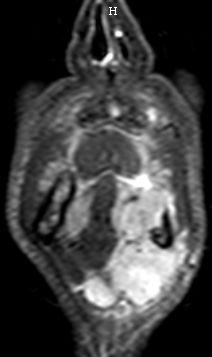

| MRT | 54-jähriger Mann mit Mundbodenkarzinom links cT4 cN2 M0. Zunächst Schmerzen im linken Unterkiefer, dann spontan Zahnausfall. Zahnarzt: kein Tumorverdacht. Dann Schwellung am vorderen Unterkiefer links. Klinisch 8 cm große, derbe, fixierte Schwellung am linken Unterkiefer, die bis zur Kinnspitze reicht und etwas auf die Gegenseite herüberreicht. Enoral Fäden nach Extraktion sichtbar. Kein Tumorulcus! Der Unterkieferknochen ist medial kranial arodiert und wird über weite Strecken vom Tumor eingeschlossen. Der Tumor durchbricht die Mundbodenebene nach kaudal und reicht bis zum Zungenbein. | ||

|